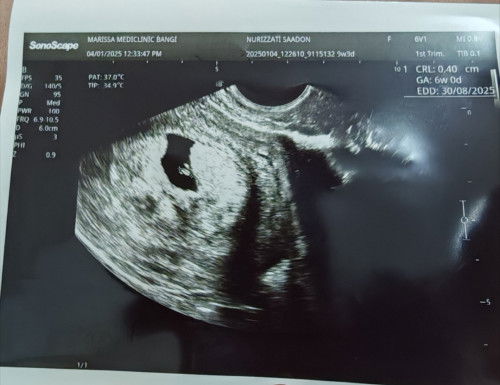

hi mommies, saya ade berlaku pendarahan keluar ketul2 warna merah pekat 2 hari lepas, pastu sy pegi klinik and scan mmg ade internal bleeding, and yg merisaukan saya doc ckp janin tak membesar jd doc kata ade miscarriage treat..doc suruh tnggu seminggu lg utk repeat scan. tp skrg darah dh kurang..die cuma keluar coklat cair je sikit..ade tak sape2 ade pengalaman mcmni..boleh ke kalau pegi kk terus sbb buat kt klinik swasta je dkt rm200 duit habis..atau pun ke kena tggu 12 week nnti baru pegi kk..#bantusharing #pleasehelp #firsttimemom